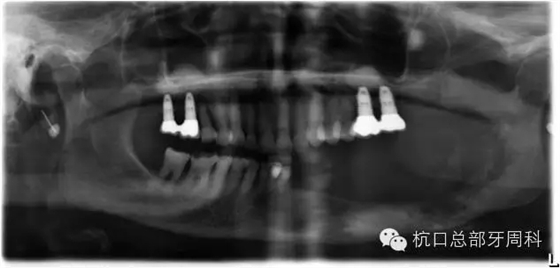

下頜所有牙齒自動脫落,炎癥累及整個下頜骨,包括左側(cè)髁狀突,病理性骨折左側(cè)聽力喪失

接下來幾個月病程惡化十分迅速,于頜面外科會診,但是考慮到患者年齡、全麻意外等風(fēng)險,下頜骨半切及重建手術(shù)方案被否決。